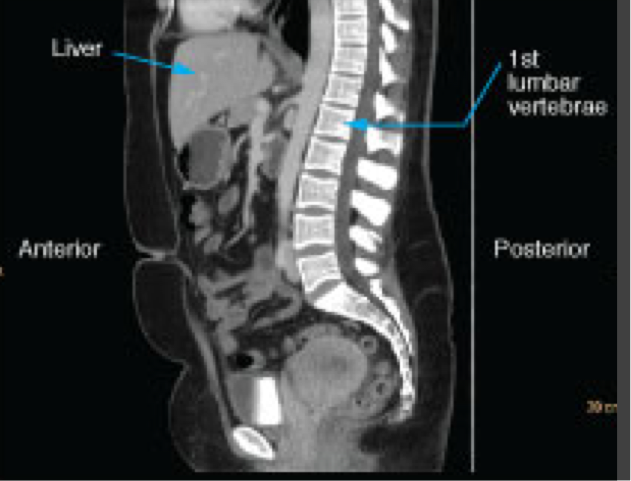

Sagittal CT images

Shown as though the patient is looking towards the viewer’s left

Abdominal and pelvic CT

Evaluating the abdominal organs for pathology such as acute abdomen or trauma